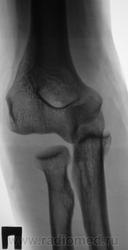

Травма.  Пациент направлен на рентгенографию локтевого сустава.

Аглицким владею (как писал раньше, заполняя различные совеЦкие анкеты) со словарем (хотя уровень этого знания таков, что никакогословаря не хватит), поэтому не могу прочитать предыдущий комментарий. А по поводу случая - я так понимаю медиальный вывих предплечья.

кости предплечья, сохраняя свое положение по отношению друг к другу, смещены в медиально и каудально. Дистальный эпифиз плечевлй кости с латеральной стороны лежит свободно (так можно писать??) Смещение в медиальную сторону составляет примерно половину ширины головки лучевой кости. Суставные поверности плечевой и локтевой кости не соприкасаются. Перелом не определяется.

Заключение: медиальный вывих предплечья ?